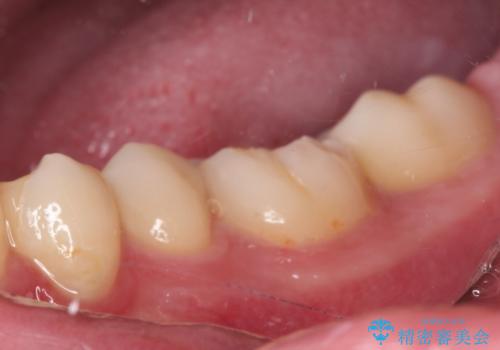

詰め物が欠けた セラミックインレーによる修復

- 以前治療した詰め物が欠けてしまったことを主訴として来院した患者様です。

食べ物がはさまったり、冷たいものがしみるといった症状がみられました。

むし歯の染め出し液と拡大鏡を用いて、むし歯がないことを確認し、

セラミックインレーにて修復することとしました。

食べ物がはさまりにくくなり、冷たいものがしみる症状もなくなり、大変満足していただきました。